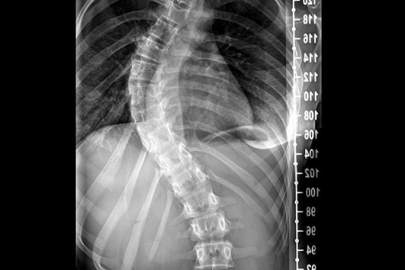

Skolyozun, özellikle büyüme çağındaki çocukları etkileyen ve omurganın anormal eğriliği ile karakterize edilen bir hastalık olduğunu söyleyen Omurga Cerrahı Op. Dr. Özgür Temiz, “Ergenlik döneminde fark edilmediğinde ilerleyebilen bu rahatsızlık, ciddi duruş bozukluklarına ve hareket kısıtlılıklarına yol açabilir” dedi.

Skolyoz konusunda aileleri uyararak erken teşhisin tedavi başarısını büyük ölçüde artırdığını vurgulayan Ortopedi ve Travmatoloji Uzmanı Op. Dr. Özgür Temiz, “Skolyoz, omuz seviyelerinde eşitsizlik, sırt ve belde asimetri, duruş bozukluğu ve bel ağrıları gibi belirtilerle kendini gösterebilir.

Eğer çocuklarda veya ergenlik çağındaki bireylerde bu belirtilerden biri ya da birkaçı fark edilirse, vakit kaybetmeden bir uzmana başvurulması gerekir” şeklinde konuştu.